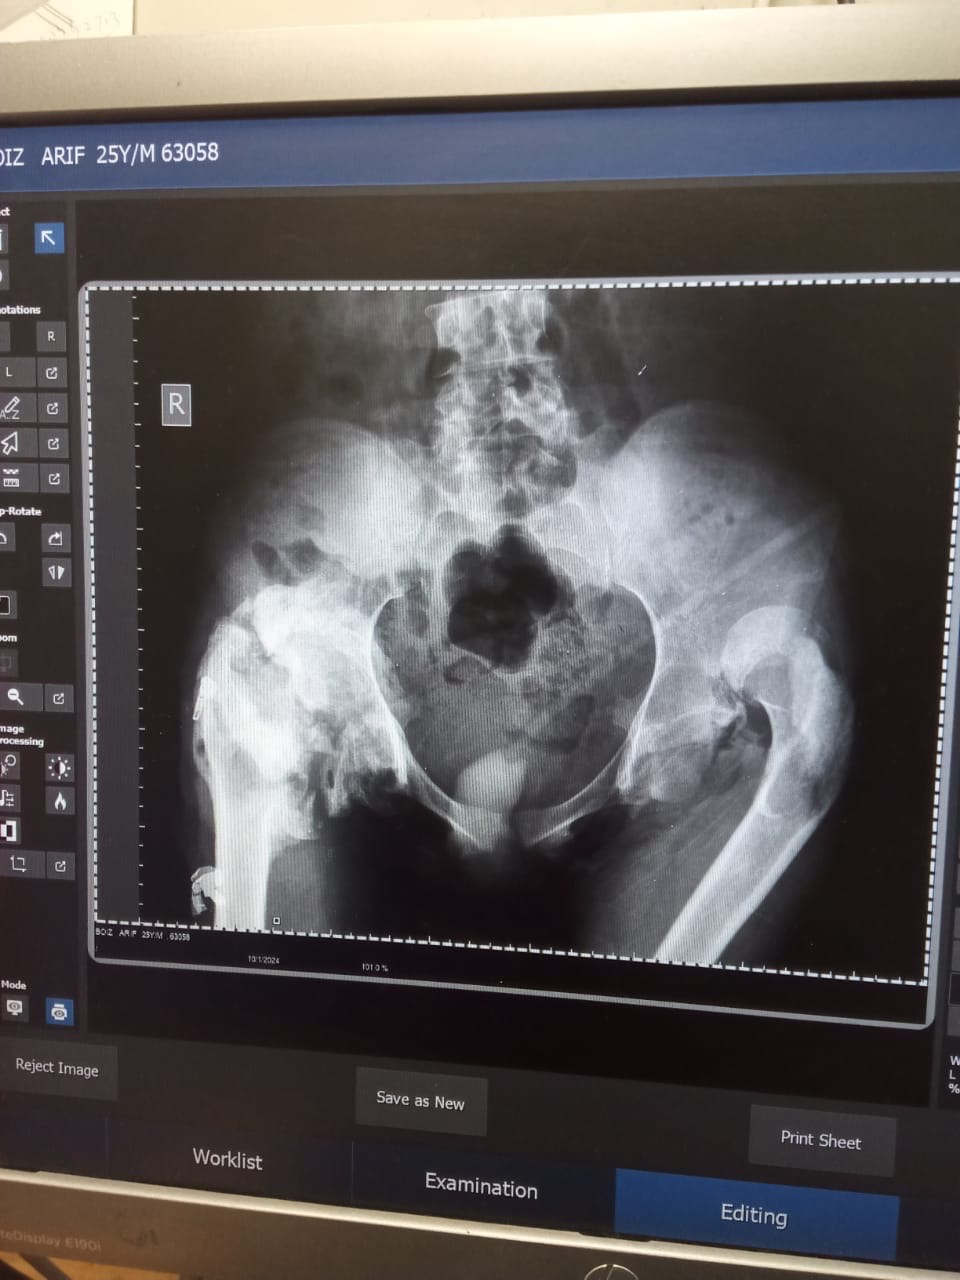

On January 10, 2020, a road accident changed my life forever. In that accident, my spine was badly broken and severely damaged. Since that day, I have not been able to walk.

I underwent a major operation, hoping to stand on my feet again, but despite the surgery, I am still confined to a bed. Because of continuous sitting and lying down, I remained bedridden for almost two years, and even now my condition has not fully improved. My back has not healed, and every day brings physical pain and emotional struggle.

As time passed, another serious problem developed. My bones have become weak, making my condition even worse. Doctors have informed us that treatment for this condition is very difficult in Pakistan and requires advanced medical care, which is beyond our financial reach.